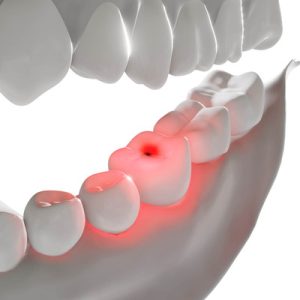

Preventing & Treating Tooth Sensitivity

Tooth sensitivity is a condition experienced by millions of Americans…